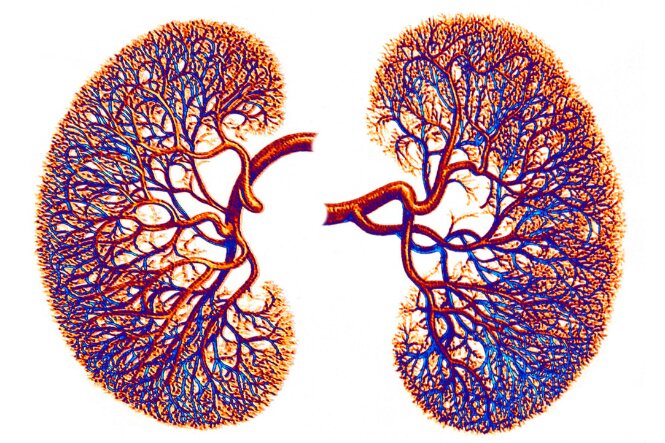

Your kidneys have a key role in your health. They filter and remove waste and excess fluid from your body. This means you need to take good care of them. Find out how to look after your kidneys, the signs they're not functioning well and more.